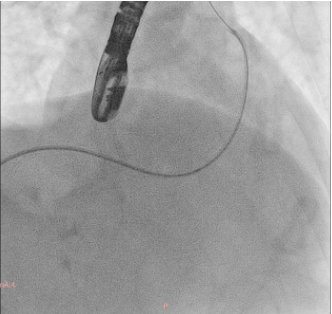

A soft hydrophilic 0.035-inch wire was directed into the RVOT, advanced distally to the right pulmonary artery, then exchanged for a super stiff 0.035-inch wire. An Armada vascular balloon 7.0x60 mm was positioned in the RVOT and inflated to 12 atm for ten cycles. An Omnilink vascular stent was deployed in the RVOT and inflated to 12 atm. Due to the patient¡¯s late presentation, a second identical stent was placed at the same location. Following the procedure, LVEF improved to 64.7%, and aortic oxygen saturation increased from 86% to 94%.